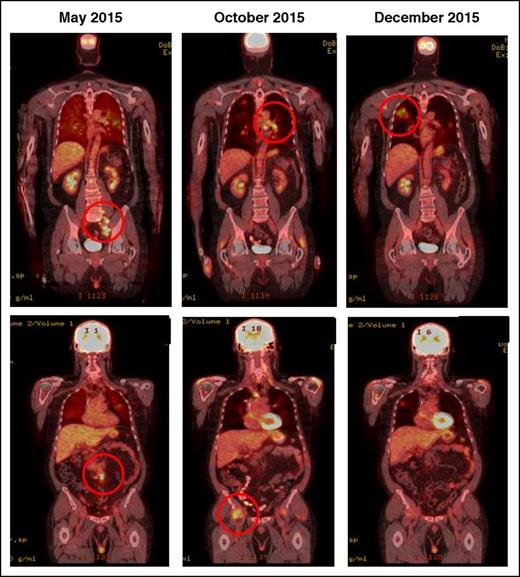

IR(2): CT demonstrating pseudo-progression in a patient on nivolumab for Hodgkin lymphoma. May 2015, pretreatment, October and December 2015 shows transient flares in different nodal groups without overall progression in the original target lesions.